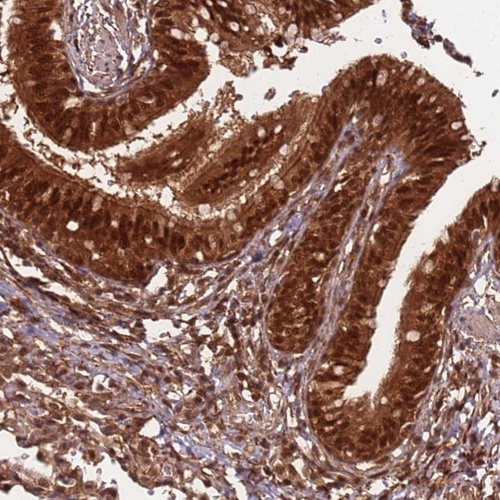

Immunohistochemical staining of human bronchus shows strong positivity in respiratory epithelial cells.